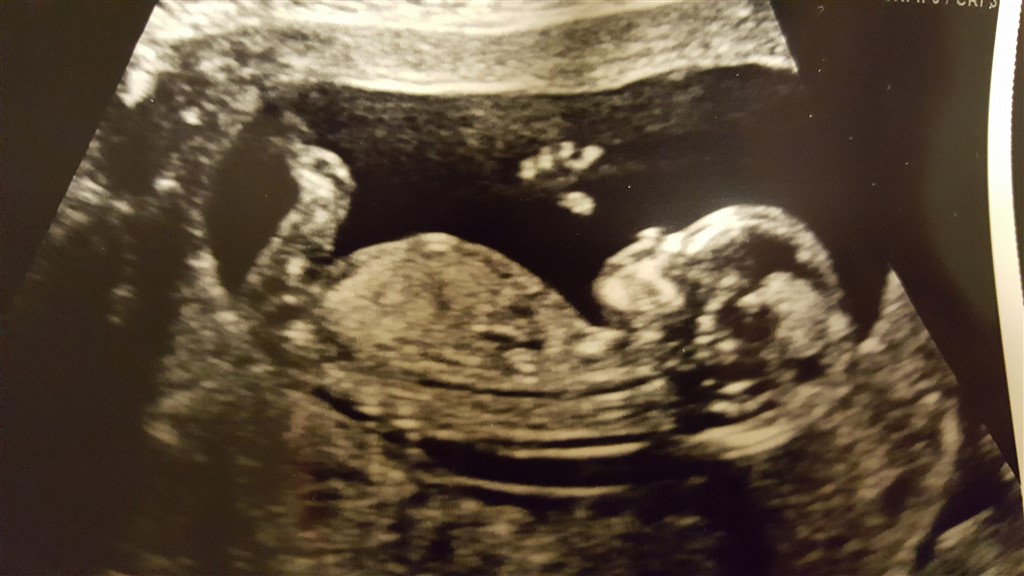

Har været til scanning og vi skal ikke vide kønnet men kan ikke lade være med at sidde og gætte.

Har 2 drenge så bliver det måske en ........??

Næææhhh... Det scanningsbillede kan jeg kende Stoooort tillykke, hvor er det fantastisk med en lille kommende skildpadde

Hmmm... Jeg gætter på dreng, aner ikke lige hvorfor... Det er sååå hyggeligt ikke at kende kønnet før fødslen